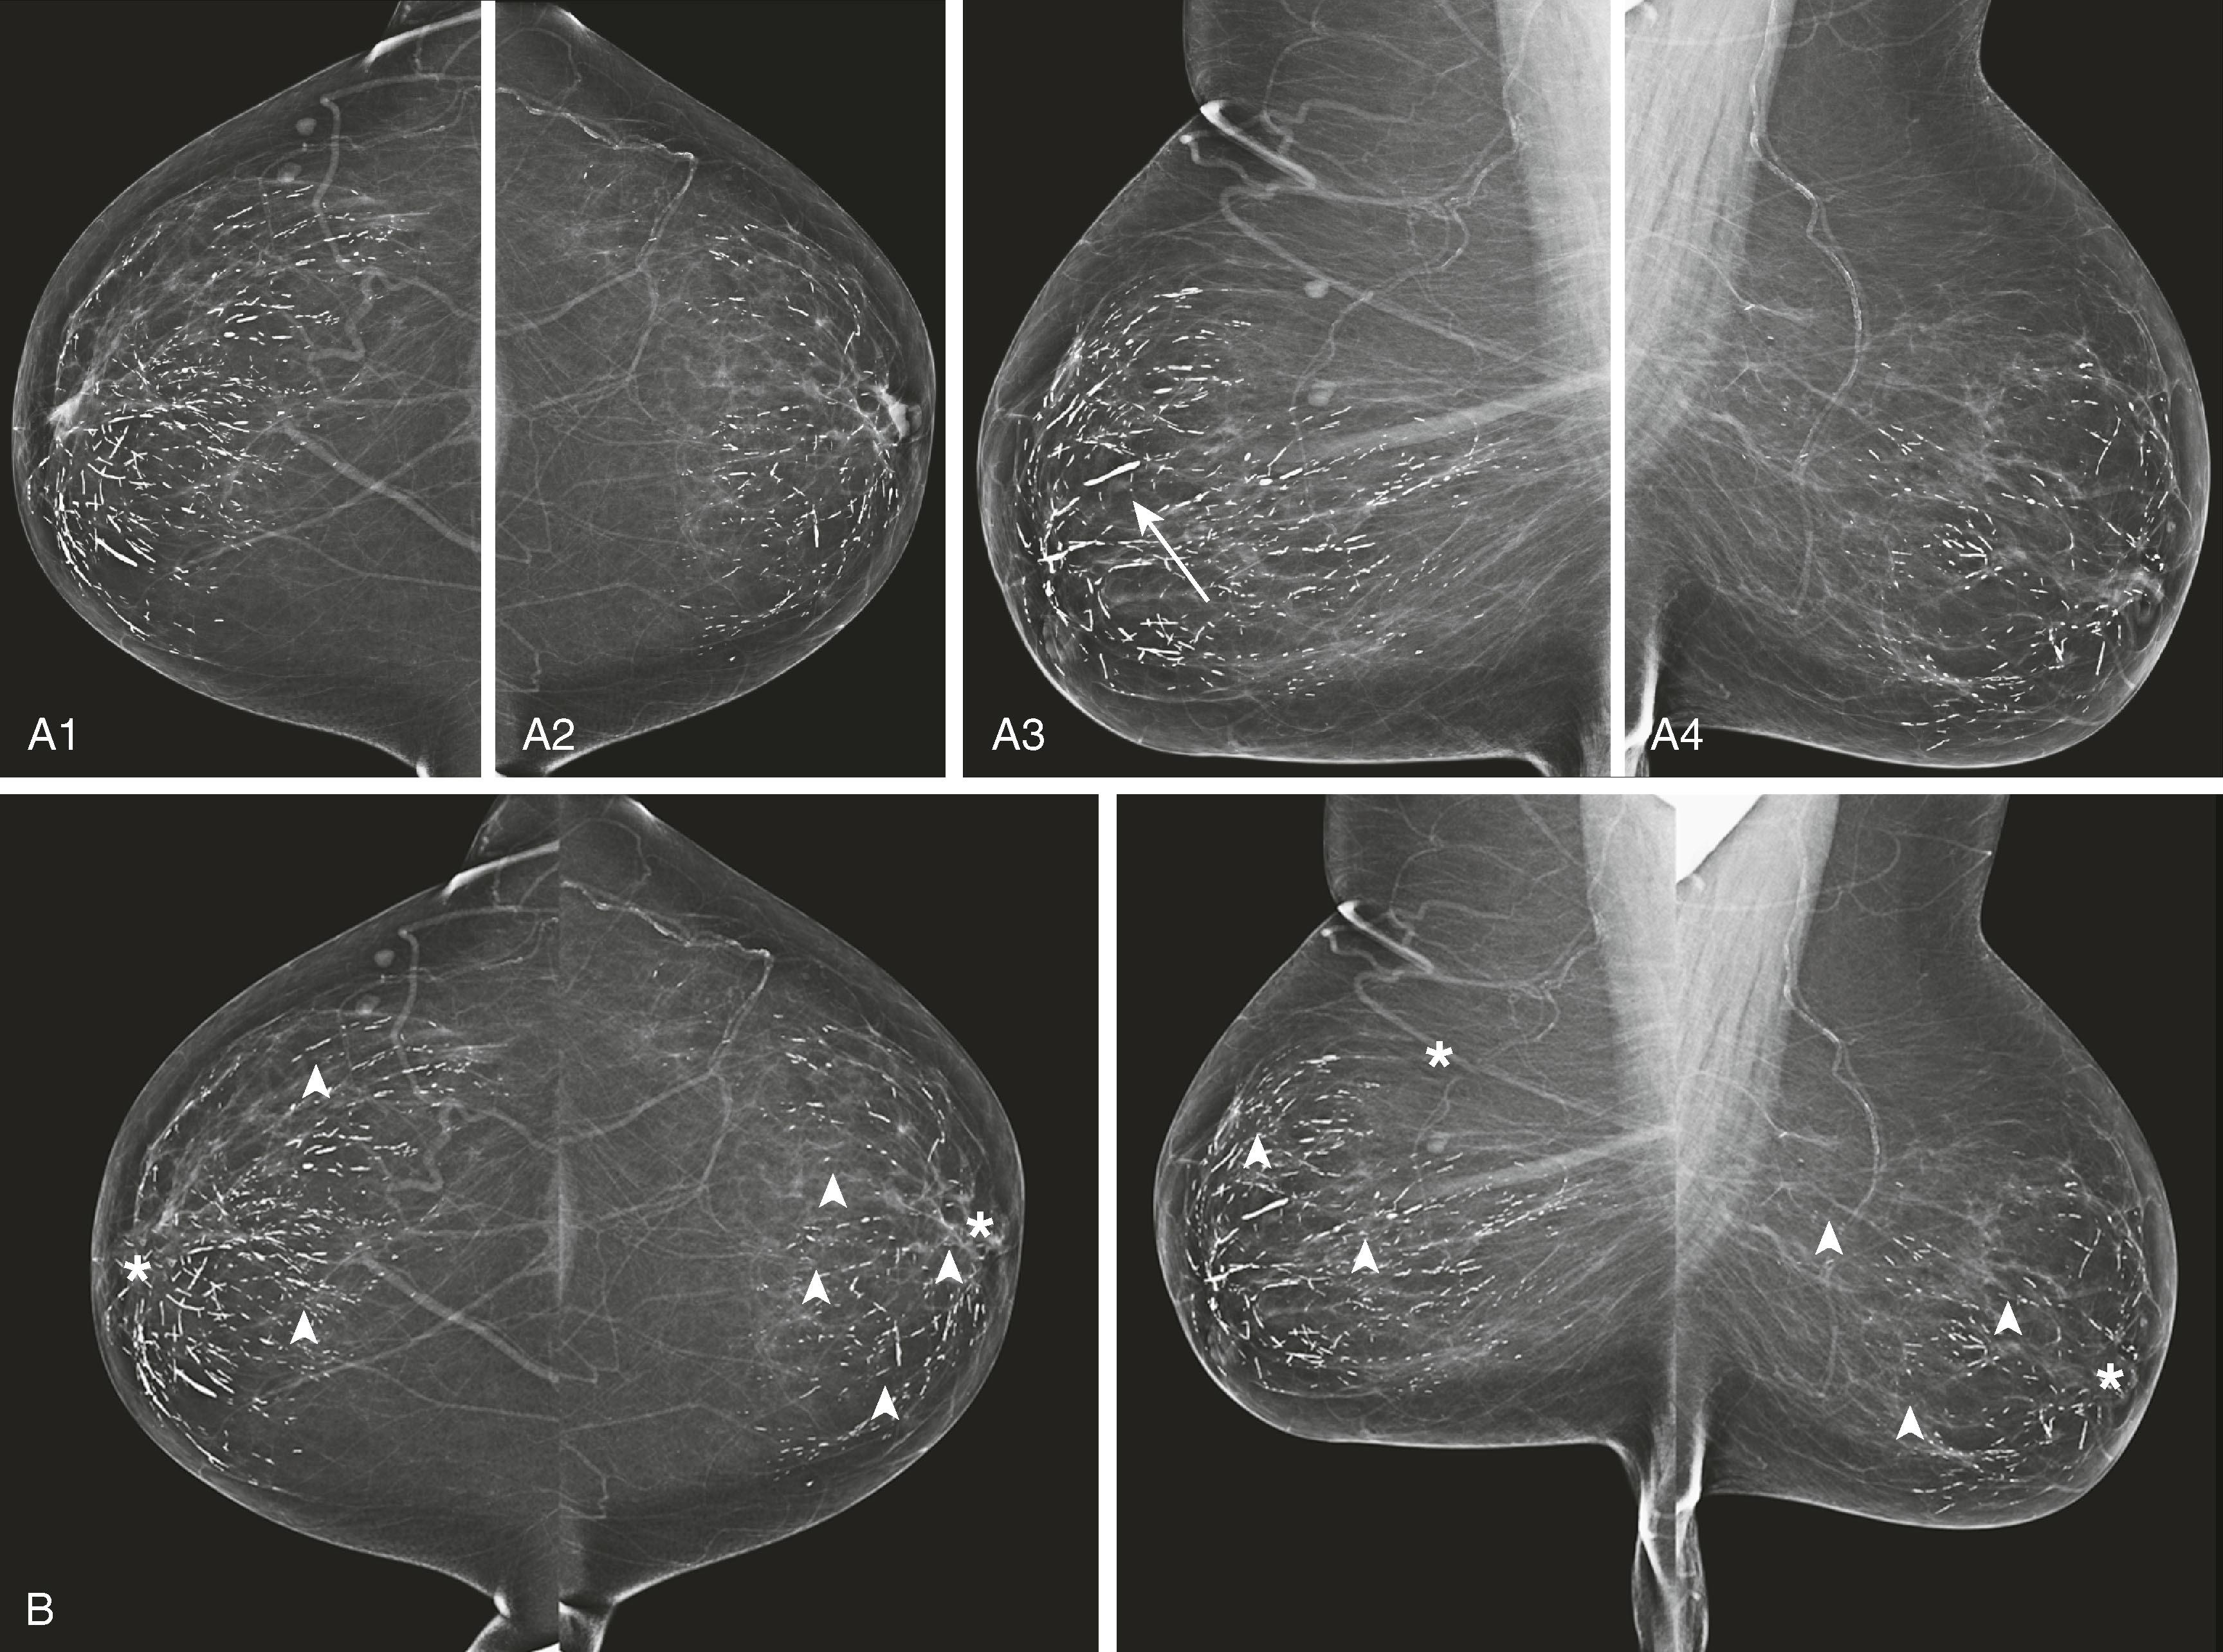

Asymmetrical densities , now called asymmetry and focal asymmetry , are sometimes attributable to malignancy but more often represent areas of glandular tissue. These are evaluated by comparison with old studies; spot compression views; angled or rolled views, often with tomosynthesis; and ultrasound. Persistence on multiple views and change from prior study suggest a true mass, which will be evaluated with ultrasound ( Figs. 8.8 and 8.9 ).

Fig. 8.8, ( A1 and A2 ) Craniocaudal (CC) and mediolateral oblique (MLO) routine images and ( B1 and B2 ) CC and ML spot magnification views of focal asymmetry reveal a spiculated mass. ( C ) Magnetic resonance imaging and ( D ) ultrasound images of the same lesion. RMCC , Right magnification craniocaudal; RMML , right magnification mediolateral.

Fig. 8.9, ( A and B ) Craniocaudal (CC) and mediolateral oblique (MLO) screening views showing focal asymmetry (arrows) . ( C and D ) CC and ML tomosynthesis slices showing with better detail that the asymmetry is a small spiculated mass (arrows) . ( E ) Sonogram depicting the subtle 5-mm mass (arrows) seen on mammography. Core biopsy revealed invasive duct carcinoma and ductal carcinoma in situ, nuclear grade 2, low Ki-67.